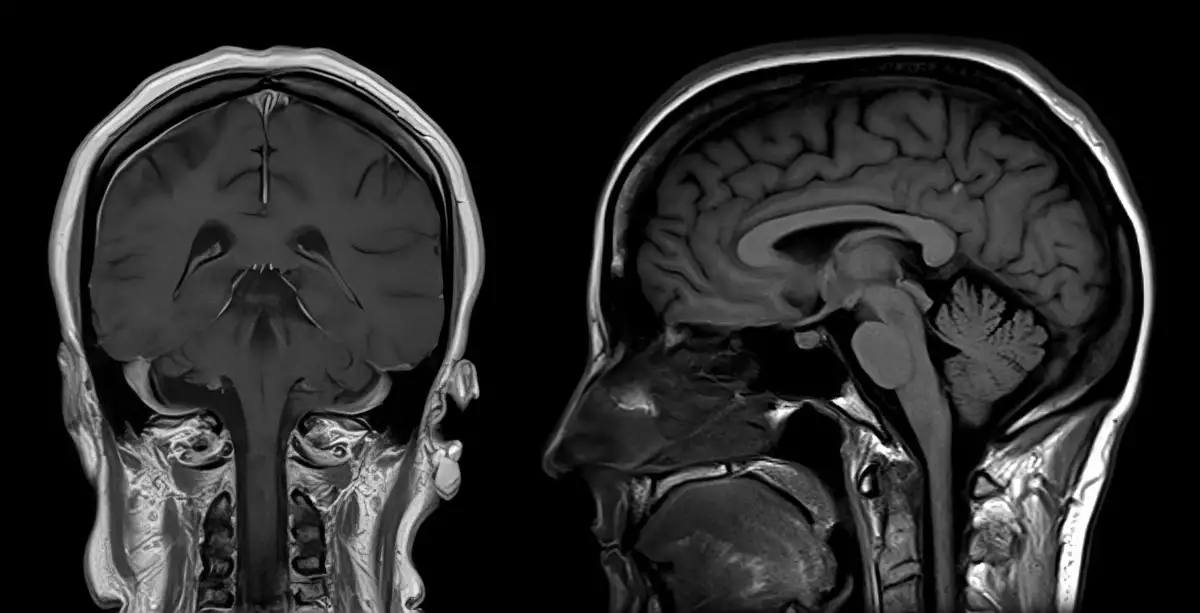

Se han realizado investigaciones para analizar la relación existente entre el COVID-19 y el tinnitus. (Foto: apomares/Getty Images)